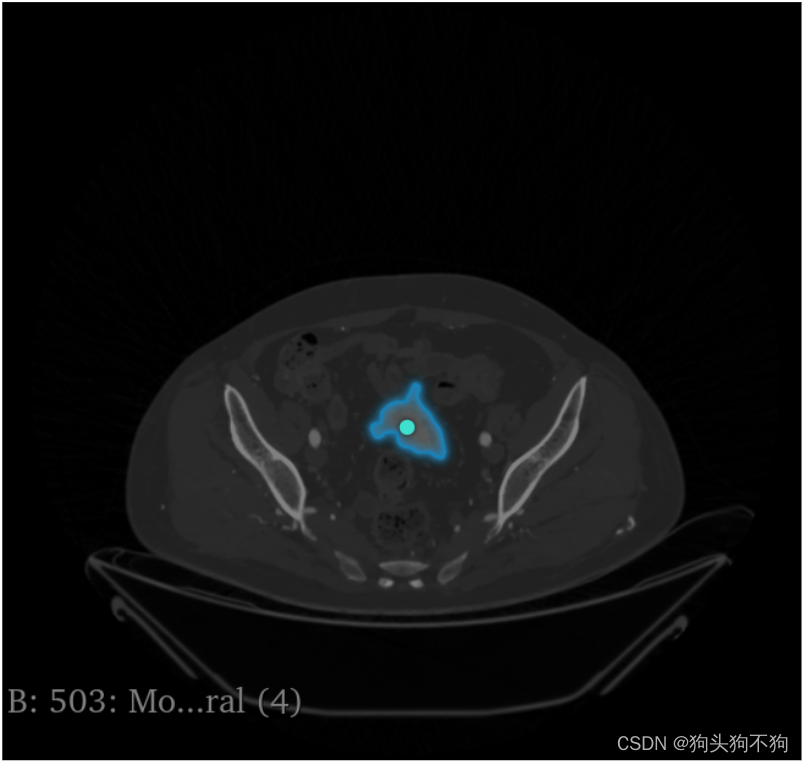

除了网站提供的图像之外,还支持自己上传图像,以人体的CT扫描图像为例

点击: